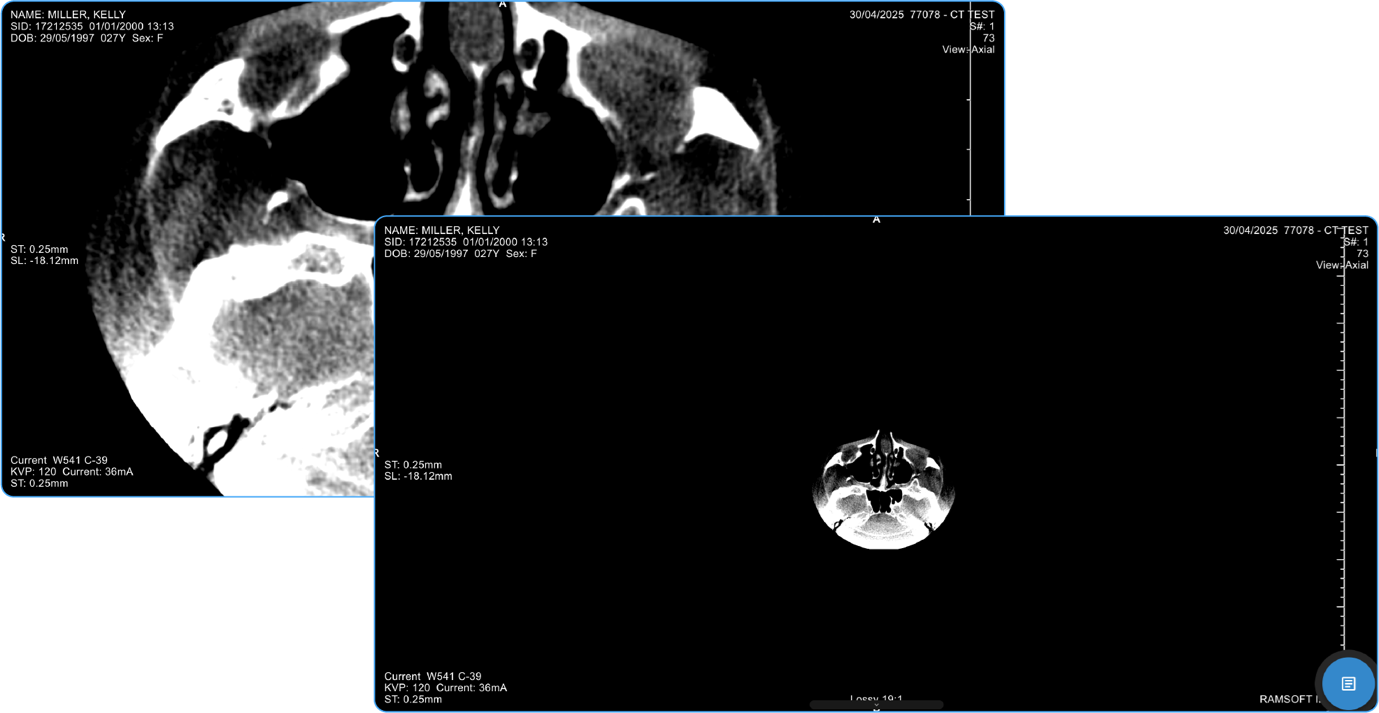

Zooming Options:

• Scroll Method: Press and hold the left-click button on your mouse and scroll up to zoom out or down to zoom in.

• Click Method: After clicking on the Zoom icon, left-click once to reveal three options:

vai

a. Actual Pixels (100%): Displays the image at its original resolution.

b. Fit to Viewport: Automatically adjusts the image to fit the viewer screen.

c. Fill the Viewport: Enlarges the image to fill the entire viewer.